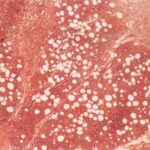

Histopathology. The histopathologic appearance itself is not sufficiently specific to exclude other diseases . The classical description of the disease is that it evolves through three stages. In the first phase, there is only erythema and induration clinically. Histologically, acute inflammation is found in the fat lobules with degeneration of fat cells and an infiltrate of neutrophils, lymphocytes, and macrophages. The second phase has an infiltrate discretely localized to the fat lobules, consisting mainly of macrophages, foam cells, and extracellular lipid droplets. In some cases, the lesions perforate the skin surface and discharge a sterile, oily liquid. The third phase |

has depressed and indurated clinical lesions. Fibroblasts, collagen, and scattered lymphocytes and a few plasma cells replace the fat. Vascular changes are mild . |